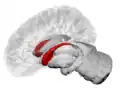

Caudate nucleus (in red) shown within the brain